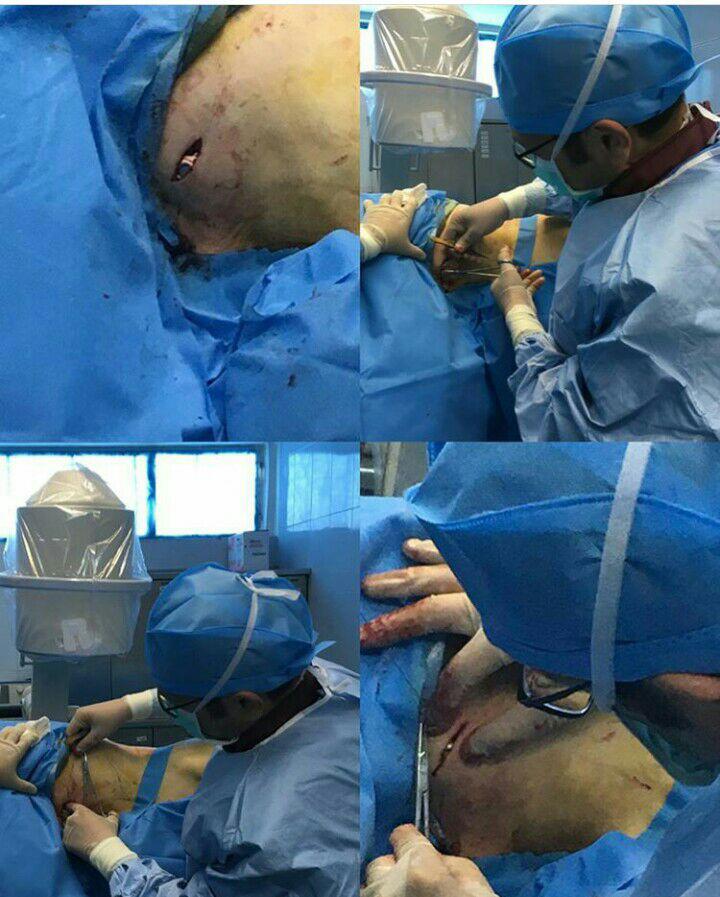

-لیزر(جراحی بسته) دیسک کمری

استفاده از روشهایی مانند تزریقات تخصصی (مانند اپیدورال، بلوک عصبی)، طب سوزنی، فیزیوتراپی، تحریک الکتریکی عصب و روشهای کم تهاجمی جراحی.